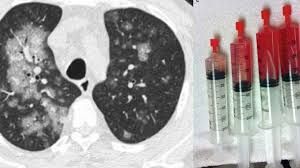

- CT-scan hộp sọ: Tạo hình ảnh 3 chiều, cho thấy xương sọ của bạn có bị bào mỏng đi hay không hoặc liệu có khối u đang tồn tại hay không.

- MRI (chụp cộng hưởng từ): Cho thấy hình ảnh chi tiết về xương sọ cũng như các cấu trúc xung quanh hộp sọ. Xét nghiệm này có thể gợi ý nguyên nhân gây ra tình trạng tiêu xương sọ.

- Xét nghiệm máu: Phát hiện tình trạng tăng bạch cầu gợi ý viêm, nhiễm trùng.